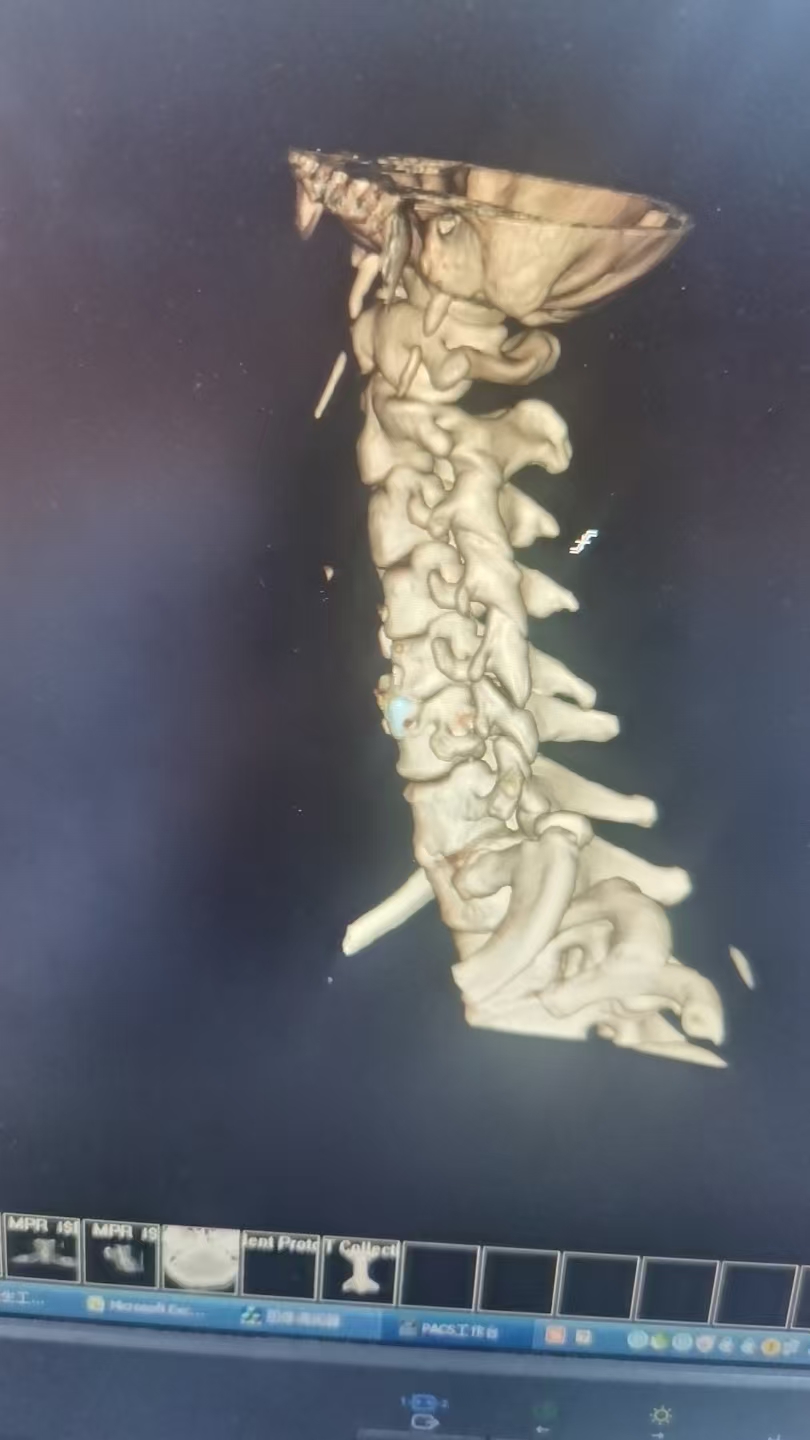

47岁李先生(化名)近日因车祸导致“颈髓损伤,四肢麻木无力”入院。经我院脊柱外科团队详细检查,影像学检查显示颈3/4及4/5节段椎间盘突出,脊髓神经根受压,引发四肢不完全瘫痪。术前右侧上、下肢体肌力:3级,左上肢肌力3级,左下肢肌力1级。

由于保守治疗效果不明显,医护团队综合评估后,决定为患者施行颈椎前路微创手术。在南医三院派驻骨科专家、东凤人民医院副院长闫慧博(挂职)的带领下,我院骨科团队共同为患者实施“颈椎3/4、4/5双节段前路椎间盘摘除+椎体融合术”。

手术借助进口微创设备完成,切口小,术中出血约20ml,历时约1.5小时,患者生命体征平稳。

(术后图)

患者术后1小时意识清醒,生命体征稳定。术后神经功能较前有所改善,特别是右侧肢体肌力已达4级,为早期开展精细活动和力量训练创造了良好条件。